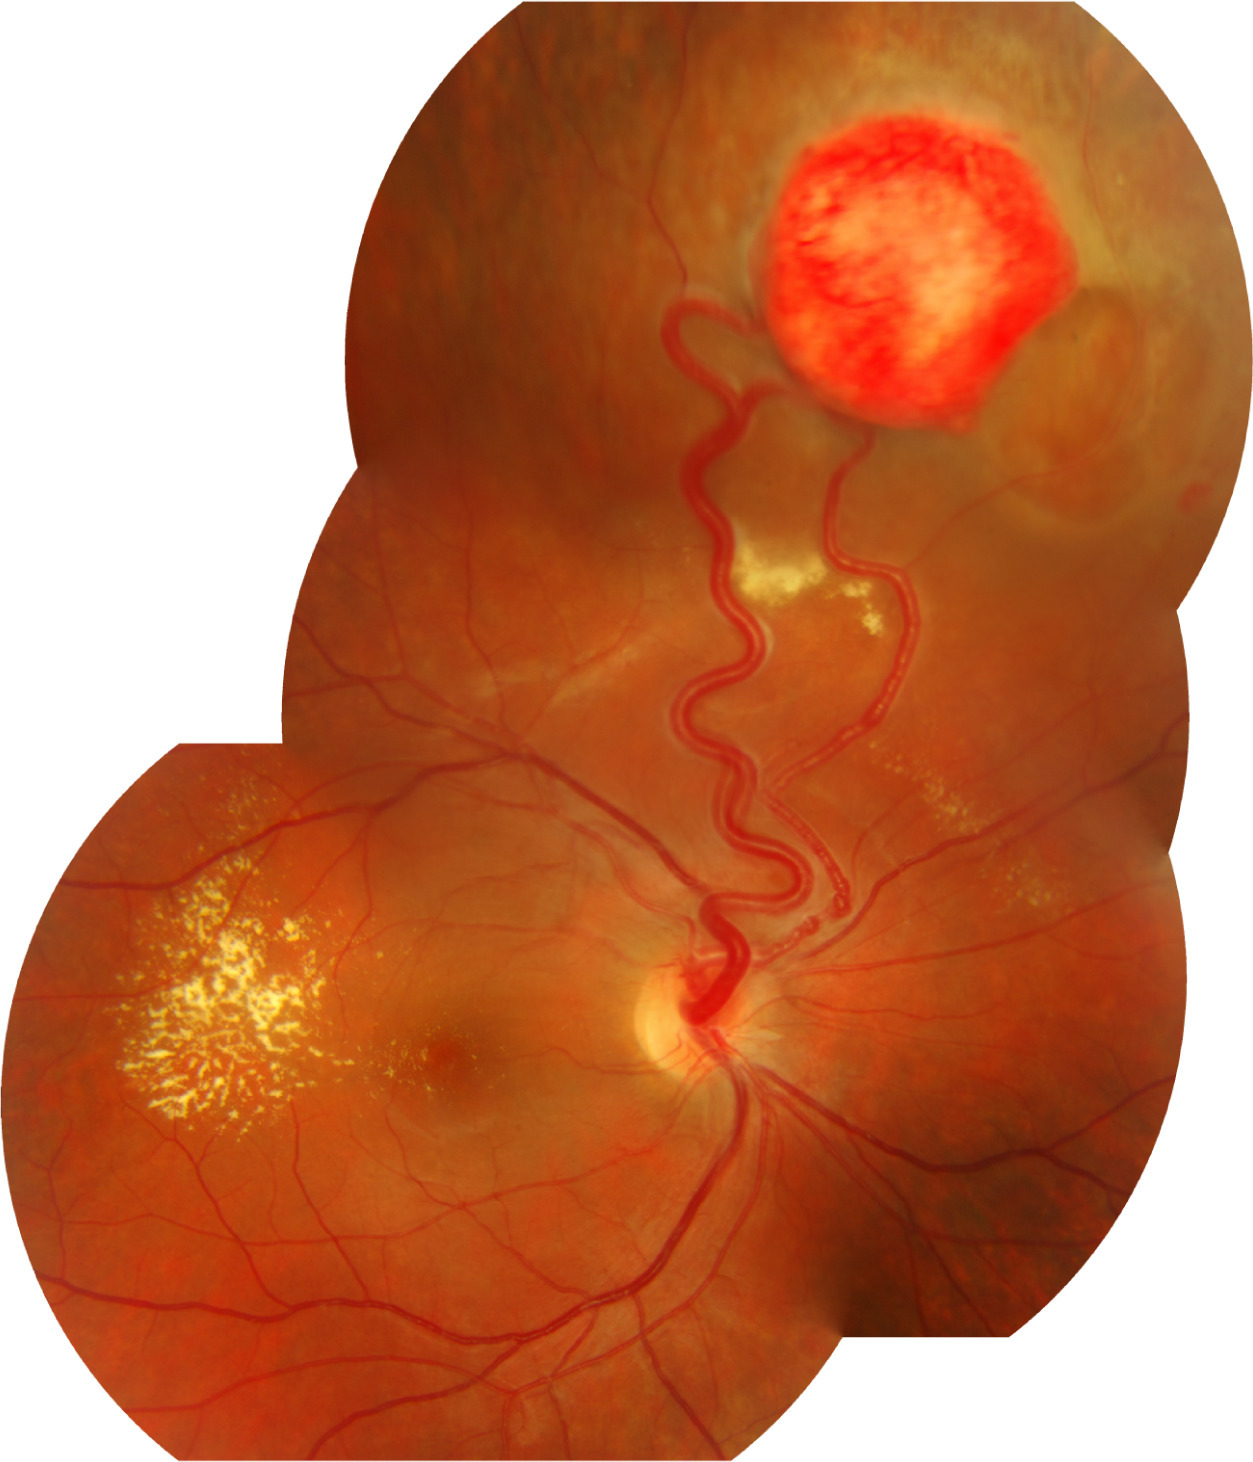

Descreva o hemangioblastoma ou hemangioma capilar?

Tumor avermelhado e arredondado formado por células angioblásticas e capilares hiperplásicos.

Quais são as principais complicações dos Hemangioblastomas?

Exsudação

DR Seroso

Hemorragia Vítrea

Quais são os achados típicos do Hemangioma Cavernoso da Retina?